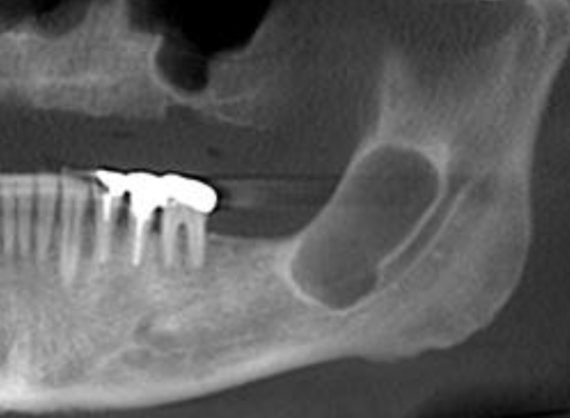

multilocular and well-defined

how would you describe this lesion?